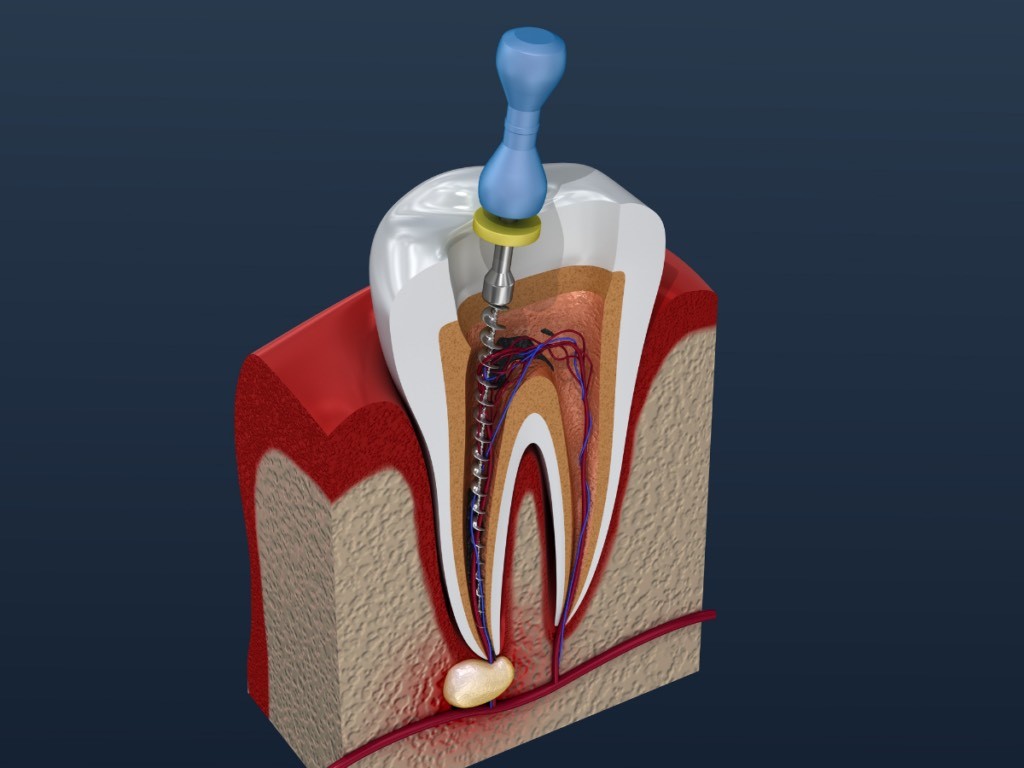

Θεραπεία Ριζικών Σωλήνων (Απονεύρωση)

Η απονεύρωση είναι η πιο συχνή ενδοδοντική θεραπεία και εφαρμόζεται όταν ο πολφός του δοντιού έχει φλεγμονή ή νεκρωθεί, συνήθως λόγω:

Διαδικασία

Διάγνωση με ακτινογραφία και έλεγχο.

Ανώδυνη αναισθησία και απομόνωση του δοντιού.

Αφαίρεση του φλεγμονώδους ή νεκρού ιστού.

Καθαρισμός και απολύμανση των ριζικών σωλήνων με σύγχρονα εργαλεία.

Σφράγιση με ειδικά βιοσυμβατά υλικά.

Τελική αποκατάσταση του δοντιού με έμφραξη ή θήκη.

Η απονεύρωση εξαλείφει τον πόνο και προστατεύει το δόντι από μελλοντικές επιπλοκές, δίνοντάς του μια δεύτερη ευκαιρία ζωής.